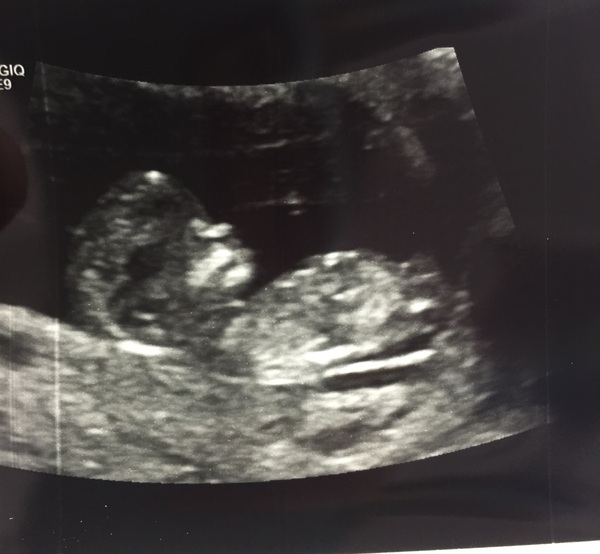

Lovely pic Jpeg!